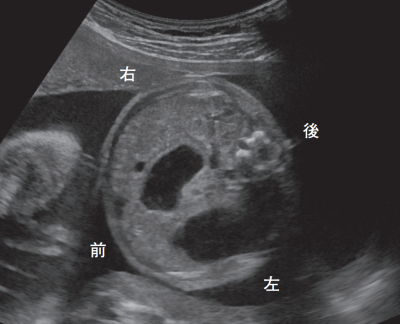

生後 4 時間の女児。胎児超音波検査で異常を指摘されていた。在胎 37 週、出生体重 2,850 g で出生した。眼裂斜上と平坦な鼻根部とを認める。胎児超音波像と出生後に撮影した胸腹部エックス線写真とを別に示す。

この児に予想される染色体核型はどれか。

e. 47,XX, +21